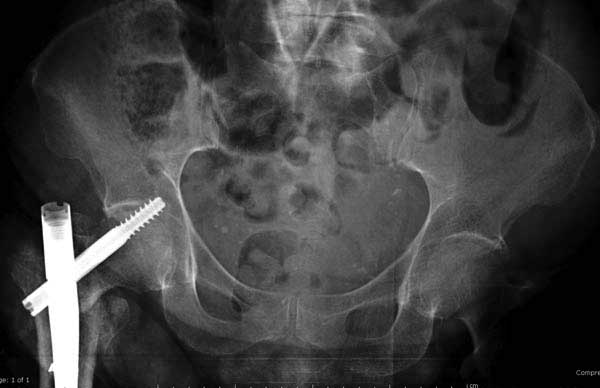

Такие “чужие осложнения” встречаются у всех и представляю банальный случай, который шаг за шагом показано как перерос в более сложный процесс... Больная 70 лет, множественные ко-морбидности, чрезвертельный перелом первоначально фиксирован Гамма 3. Осложнение в течение 6 недель, ревизия тотальной артропластикой и во время установки ножки обнаружена трещина диафиза (17), из малого доступа фиксация алло-графтом.

Обычно после чрезвертельных переломов, за исключением молодых, у пожилых остается нестабильность при движении. Часто падают и после 3х мес. в результате падения обнаружен перипротезный перелом (22-23), который зафиксирован Синтез пластиной.

Повторно поступает после двух с половиной лет, где обнаруживается перелом на второй стороне. Немного сложно, но для фиксации выбрали Antegrade InterTan Smith Nephew Nail и с момента фиксации более 3х мес.